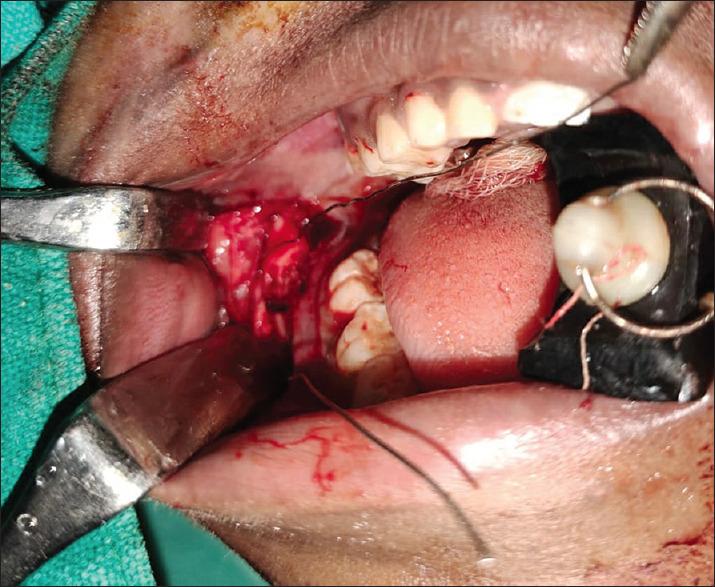

After raising a full-thickness mucoperiosteal flap, the fracture segments are identified and reduced. 1.6mm drill bit is used to make holes through the buccal cortex on either side of the fractured segment in an anteroposterior direction. The patency of holes is checked by passing a long 26-gauge wire. The proximal end of the wire is bent into a loop, a 2-0 resorbable polyglactin suture (vicryl) is passed through this loop and the loop is pressed in place to lock the suture. The wire with the attached suture is pulled through the distal end. Once the suture is secure in place, the 26G wire is cut, and the two ends of sutures are knotted and stabilised. The mucoperiosteal flap is then closed.

在掀起全厚黏骨膜瓣后,识别并复位骨折段。使用 1.6mm 钻头在骨折段两侧的颊侧皮质上从前向后方向钻洞。通过穿过长 26 号钢丝检查孔的通畅性。将钢丝的近端弯曲成一个环,将 2-0 可吸收聚乙交酯缝线(薇乔线)穿过这个环,然后将环压到位以锁定缝线。将带缝线的钢丝穿过远端。一旦缝线固定在位,就剪断 26G 钢丝,将缝线的两端系紧并固定。然后关闭黏骨膜瓣。